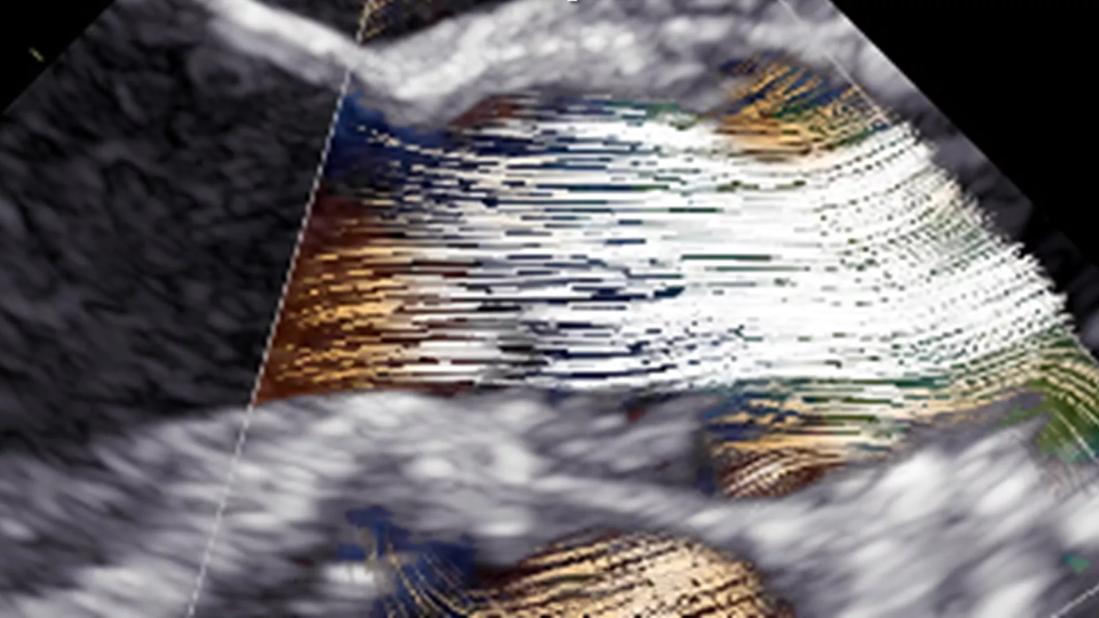

Blood speckle imaging of the aortic valvar leaflets

Figure. An example of blood speckle imaging before and after resection of a subaortic membrane with repair and rehabilitation of the aortic valvar leaflets demonstrates improved, laminar blood flow during systole.

The preoperative images revealed abnormal blood flow patterns and high peak velocity associated with obstruction of left ventricular outflow and restricted valvar leaflets. With resulting resolution of stenosis and only trivial regurgitation, the postoperative BSI assessment, in contrast, showed improved, more laminar hemodynamic patterns and improved shear stress both on the leaflets and aortic walls.